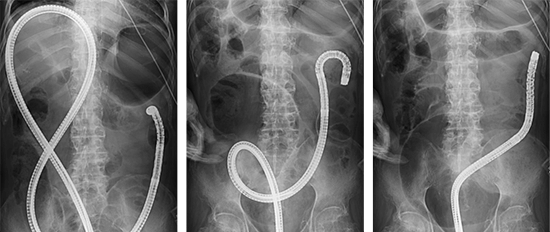

S状結腸軸捻転に対する緊急内視鏡的整復術

腸の一部がねじれて便が通らなくなる病気で内視鏡を使ってねじれを解除し、腸の通過を回復します。

下行結腸癌に対する緊急大腸ステント留置術

大腸が、がんなどで腸閉塞を来した場合に、金属製のステントを内視鏡で挿入し、通過を確保します。